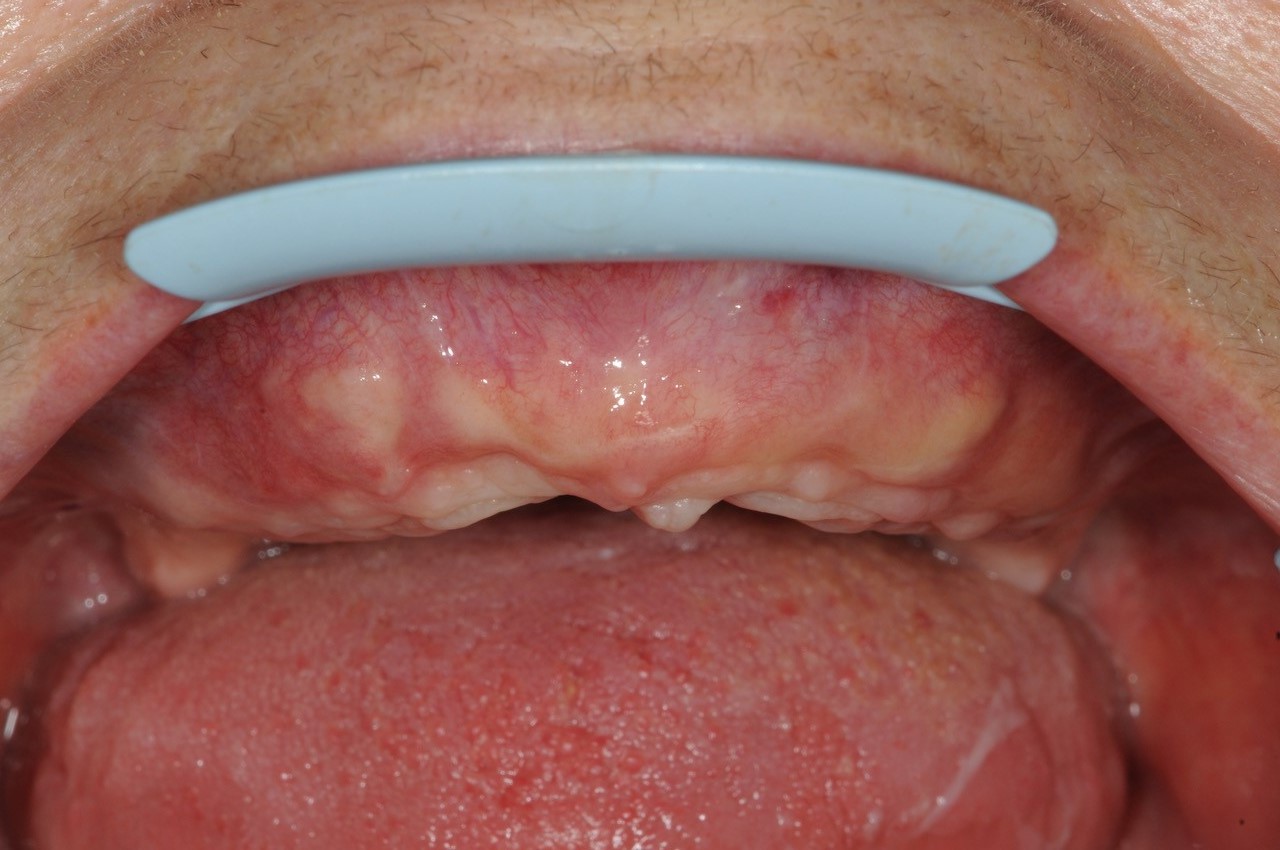

15/21 - 6 months post-op uneventful healing

Reconstruction of maxillary ridge with maxgraft® block - Amit Patel

16/21 - 6 months post-op uneventful healing / crestal view